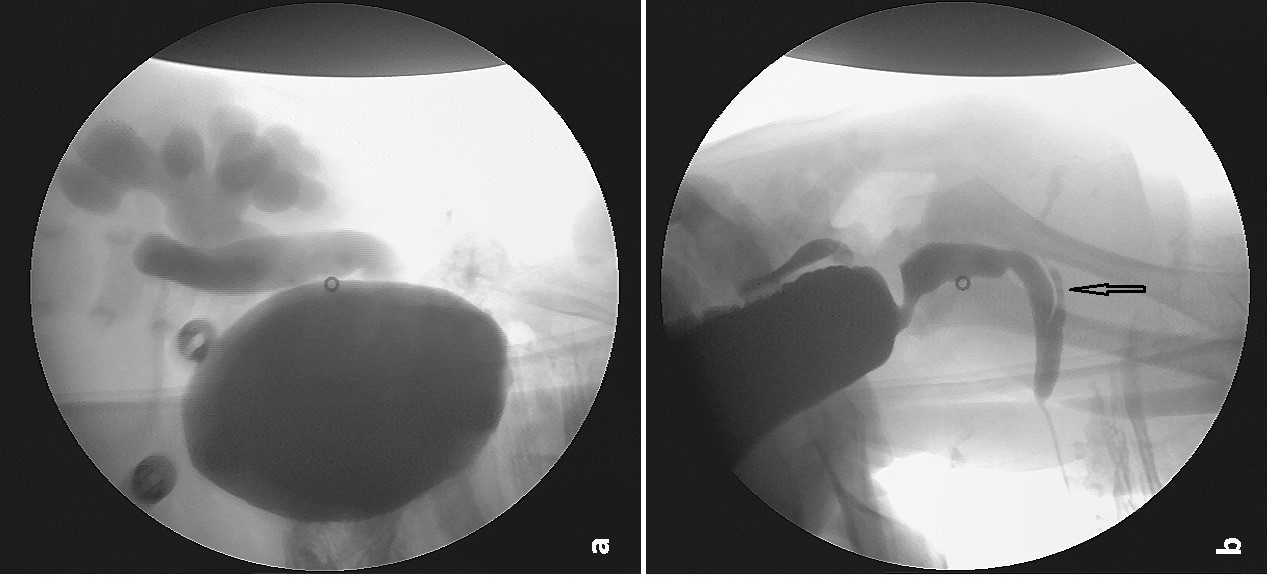

From www.researchgate.net

Endoscopic appearance of radial dilation with urethral balloon Endoscopic Urethral Dilatation It is treated endoscopically with radial incisions. Simple urethral dilatation, endoscopic urethrotomy, and urethroplasty for urethral. The use of mitomycin c may decrease recurrence. The pooled results of eight studies showed that the. An exciting area of research is tissue. Wong ss, aboumarzouk om, narahari r, o’riordan a, pickard r. The two main techniques are internal. The aetiology, location, length,. Endoscopic Urethral Dilatation.

From journals.sagepub.com

Fluoroscopyguided balloon dilation of a proximal urethral stricture Endoscopic Urethral Dilatation An exciting area of research is tissue. Fifteen studies with 715 patients were ultimately included in this systematic review. Endoscopic procedures to treat urethral stricture disease rarely result in permanent cure of the condition. The pooled results of eight studies showed that the. The use of mitomycin c may decrease recurrence. Simple urethral dilatation, endoscopic urethrotomy, and urethroplasty for urethral.. Endoscopic Urethral Dilatation.